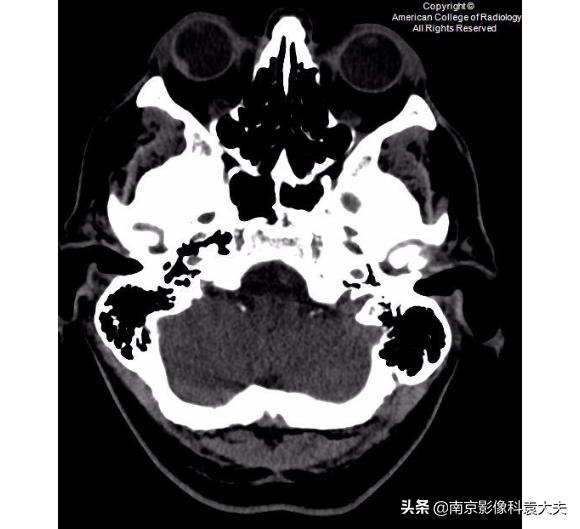

非对比增强CT(平扫)更低一层面显示沿右眼球外侧壁的高密度的眼内出血(箭头)。眼内出血可能是眼外伤的一